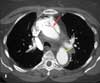

CT scan with contrast. Intravenous contrast is administered and a set of images with contrast is produced. These images are obtained in the arterial phase. The first of these, in the axial plane, is at the level of the right main pulmonary artery (D). This image shows an enlarged ascending aorta with an intimal flap (D, red arrow), consistent with dissection of the ascending aorta. The descending aorta is normal in caliber without evidence of an intimal flap (D, yellow arrow).